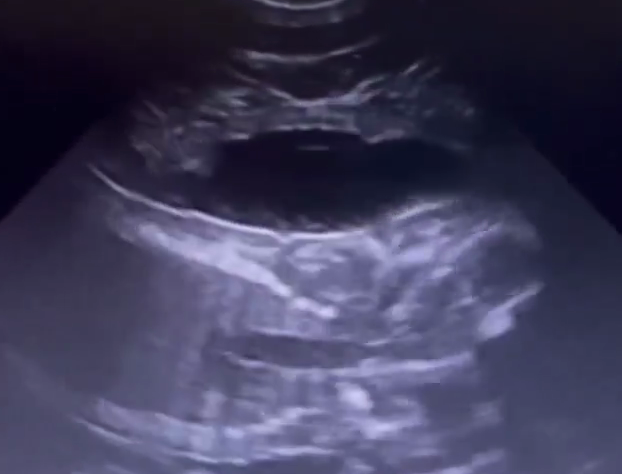

新加坡野生动物保育集团14日在社交媒体上传了三段视频,在视频中,动物护理团队指出胎儿的头部、心脏和手脚位置。动物护理团队告诉网民,小动物出生后会变色,它的妈妈喜欢咀嚼苹果和胡萝卜。